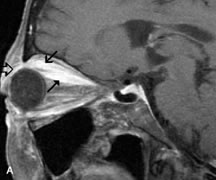

Neural Lesions

MRI is more effective than CT in delineating the intracranial optic nerves, chiasm, and optic tracts and, for this reason, is the preferred imaging modality in the evaluation of optic nerve disorders. The spatial relationships and image contrast of the orbital tissues with intraorbital optic nerve tumors is comparable between the two imaging modalities. The normal nerve is isointense to brain and appears enlarged and kinked owing to infiltration of an optic nerve glioma on T1-weighted images. Gliomas appear hyperintense on T2-weighted images and may be heterogeneous owing to cystic areas within the tumor. Contrast enhancement is variable.46

Intraorbital and intracranial optic nerve sheath meningiomas are usually isointense to cortical gray matter on Tl-weighted images and remain isointense on proton density studies (Fig. 15). Gd-DTPA is useful in delineating the intracranial extension of optic nerve meningiomas.7,47 The hyperostosis of bone and calcification associated with meningiomas are not demonstrated as well on MRI studies as on CT scans.20,37 Gd-DTPA–enhanced MRI also appears promising in the study of the permeability of the blood–brain barrier in selected optic neuropathies.22,48 MRI may reveal an enlarged optic nerve and some degree of contrast enhancement in cases of optic neuritis.49

Fig. 15. A. T1- and (B) T2-weighted MR scans demonstrate a mass causing fusiform enlargement of the optic nerve sheath complex. The peripheral portion of the mass, representing the meningioma, is isointense to brain on the T1-weighted scan and notably hypointense on the T2-weighted scan. The central portion of the mass, representing an edematous optic nerve, is very hyperintense on the T2-weighted scan (arrow), C and D. Postcontra fat-suppressed T1-weighted scans demonstrate intense peripheral enhancement of the meningioma surrounding the central nonenhancing optic nerve (arrow). Also note the enhancing Intracranial “dural tail” (double arrow).